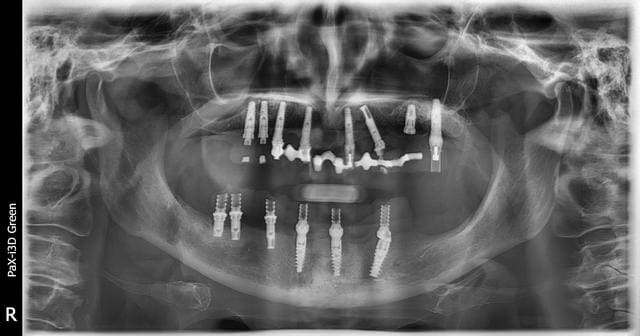

Identification implants Maxillaire et Mandibulaire

J'ai recu cette patiente au cabinet et je cherche les différentes marques implantaires et les diamètres implantaires.

je dirais que du nobel MK3 Active et replace ....

bon comme dirait Pluton faudrait des retro alveolaires ...mais mis à part les 3 implants symphysaires... pour le reste je suis pas optimiste

replace, MK3 et Active...des rétros pour être sûr à 100% mais çà y ressemble quand même beaucoup...;-)